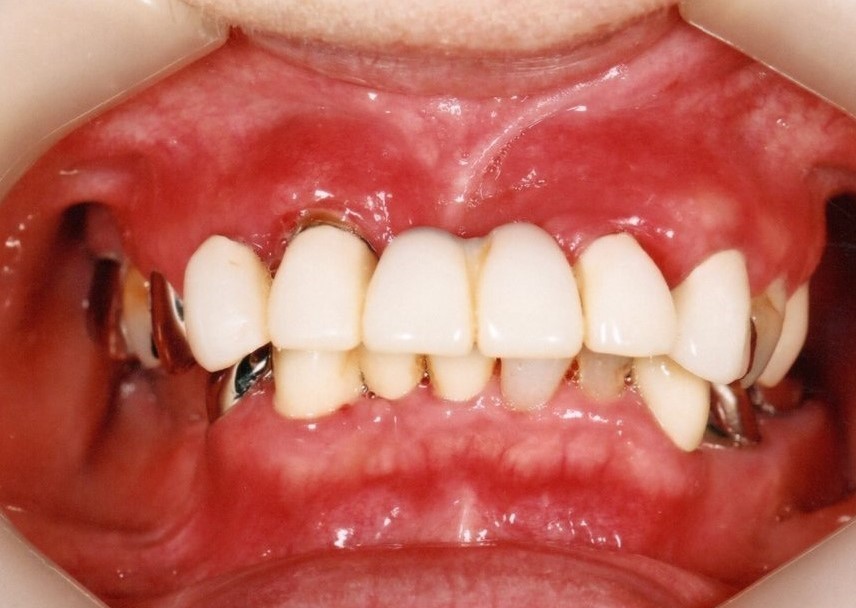

入れ歯装着前

入れ歯は一般的には歯を多く失った時に行う治療法で、型を取って、噛み合わせを記録して製作する取り外し可能な物です。保険で製作できますが、薄くて快適な入れ歯や、バネのないノンクラスプデンチャーは自費治療になります。

入れ歯

入れ歯は粘膜の上に乗せているだけなので噛むと沈み込み、土台の歯にバネの栓抜き効果が加わり、その歯が数年でダメになります。更に骨も経年と共に吸収していくので、合わない入れ歯を使用していると、更に悪化の速度が増します。